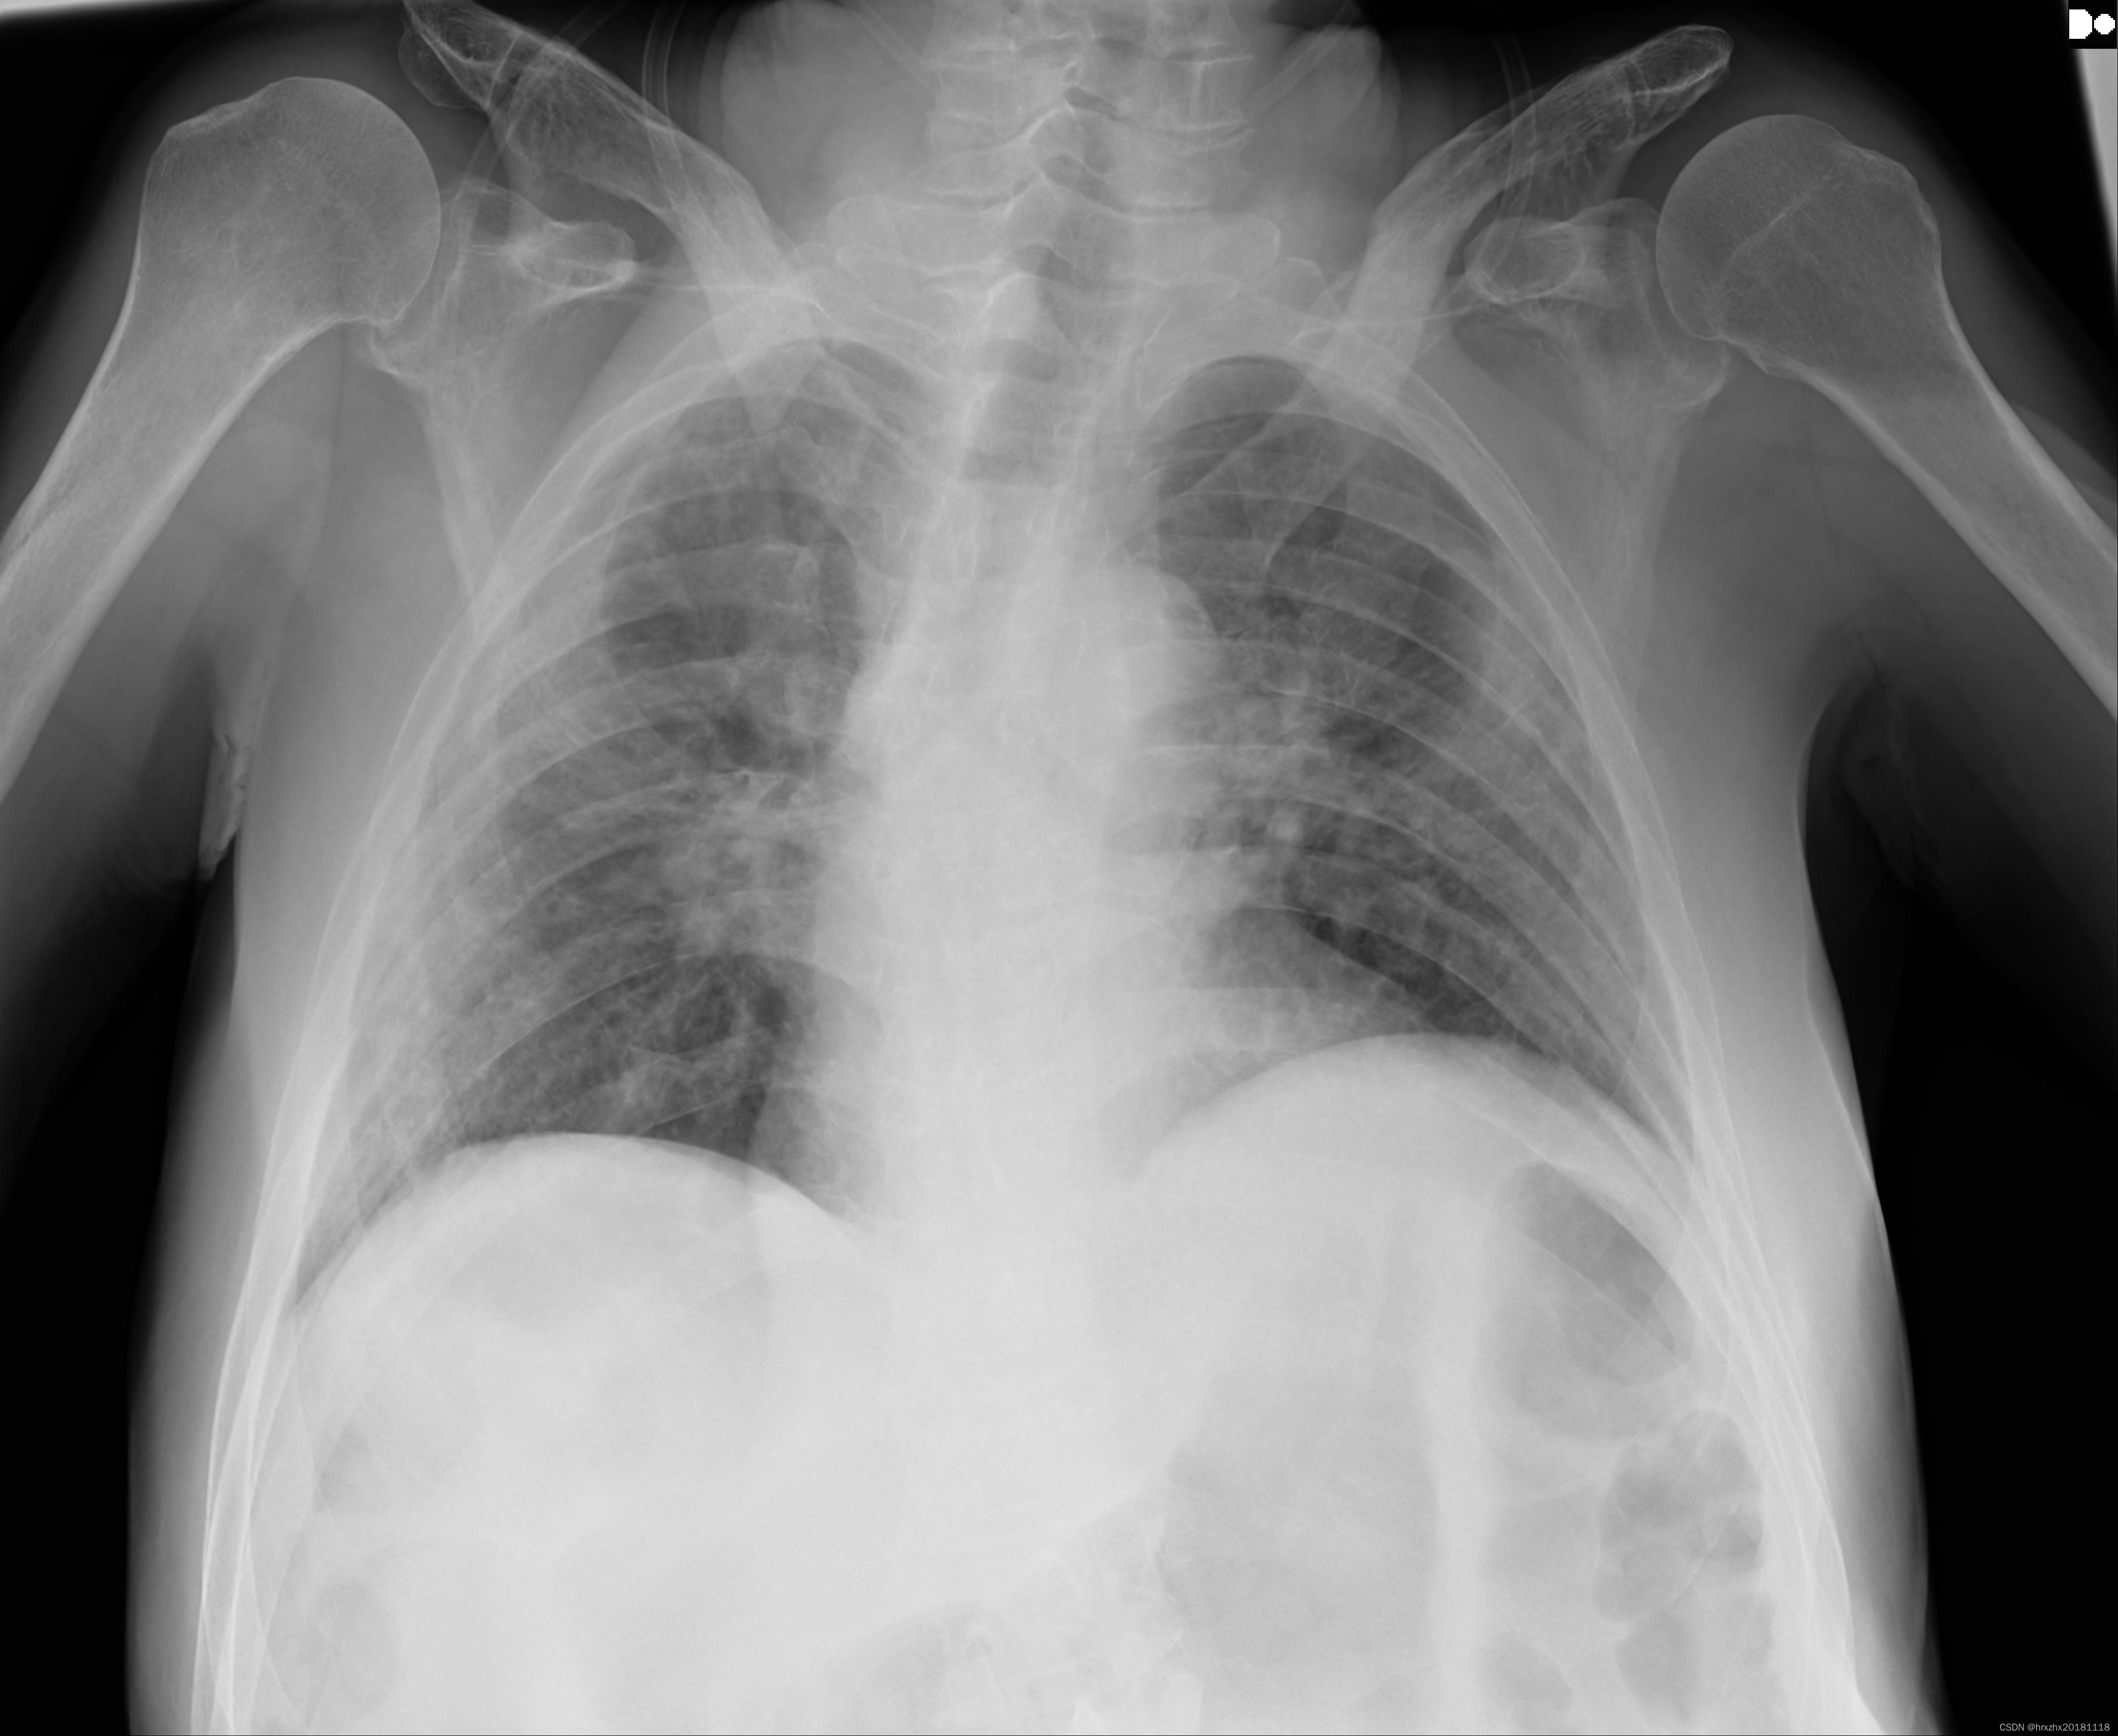

SIIM-FISABIO-RSNA COVID-19 数据集是一个专为 𝛄𝛄𝛄 疫情做出响应的服务性医学影像数据库项目。该项目由 𝛄𝛄𝛄、 𝛄𝛄𝟀 和 𝛄𝟀𝟀𝟀 三个组织共同推出,旨在推动全球研究人员对 𝛄𝟀𝟀 病毒相关肺部病变的认识与研究工作。该数据库整合了来自全球不同医疗体系中的胸部 CT 成像资料,其中包括确诊感染 𝛄𝟀𝟀 病毒及健康对照组患者的影像资料。所有影像通过匿名化处理,以确保患者隐私不受侵犯。在数据库中,每张影像均被详细标注出是否存在 𝛄𝟀𝟀 病毒相关病变,以及病变的具体位置与类型等关键信息,从而为研究人员提供了丰富的研究资源

处理好后的VOC格式的数据集图像总数为5812张,类型标签为病灶区域。